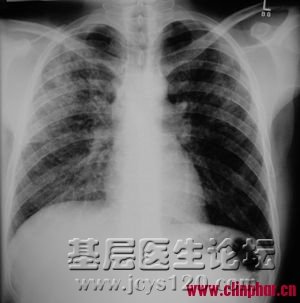

同行帮给看一下这个造影,需要怎么治疗比较理想